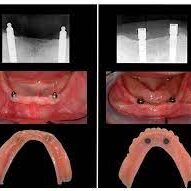

Dental Implant Placement

- Surgical Procedure:

- Placing dental implants in the jawbone under local anesthesia. Typically, 2-4 implants are placed in each arch.

Creating and Fitting the Overdenture

- Impression:

- Taking precise impressions or digital scans of the jaw and implants.

Attaching the Overdenture

- Attachment Pieces:

- Fitting attachment pieces to the implants, which will hold the overdenture securely in place.

- Overdenture Placement:

- Placing the overdenture so that it “snaps” onto or connects securely to the attachment pieces on the implants.